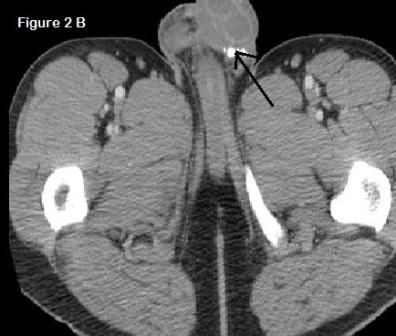

Figure 2. Isolated calcific nodules in the scrotum without extension to testicles (arrow).

A non-contrast CT scan of the abdomen showed partially visualized calcified nodules in his scrotum (Figure 2). The nodules were excised under local anesthesia, and the specimens were sent to pathology. On histologic examination, the dermis and epidermis appeared normal without inflammatory cells or atypia seen in the surrounding tissue (Figure 3). On H&E stain, there were multiple purple crystalline areas without any epithelial lining consistent with calcium deposits (Figure 4). Result of repeated excision of the remaining nodules was consistent with the initial pathology report. Parathyroid scan was normal and ruled out an adenoma.